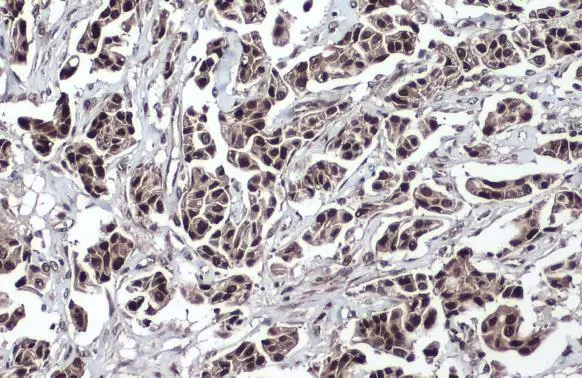

Anti-TET2 antibody [N2-2], N-term used in IHC (Paraffin sections) (IHC-P). GTX124205

GTX124205 IHC-P Image

TET2 antibody [N2-2], N-term detects TET2 protein at nucleus by immunohistochemical analysis.

Sample: Paraffin-embedded human breast carcinoma.

TET2 stained by TET2 antibody [N2-2], N-term (GTX124205) diluted at 1:500.

Antigen Retrieval: Citrate buffer, pH 6.0, 15 min